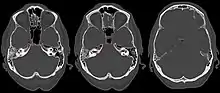

| Apicitis petrosa as seen in computed tomography | |

In persons with longstanding ear infection and typical symptoms, medical imaging such as CT or MRI of the head may show changes that confirm disease involvement of the petrous apex of temporal bone.